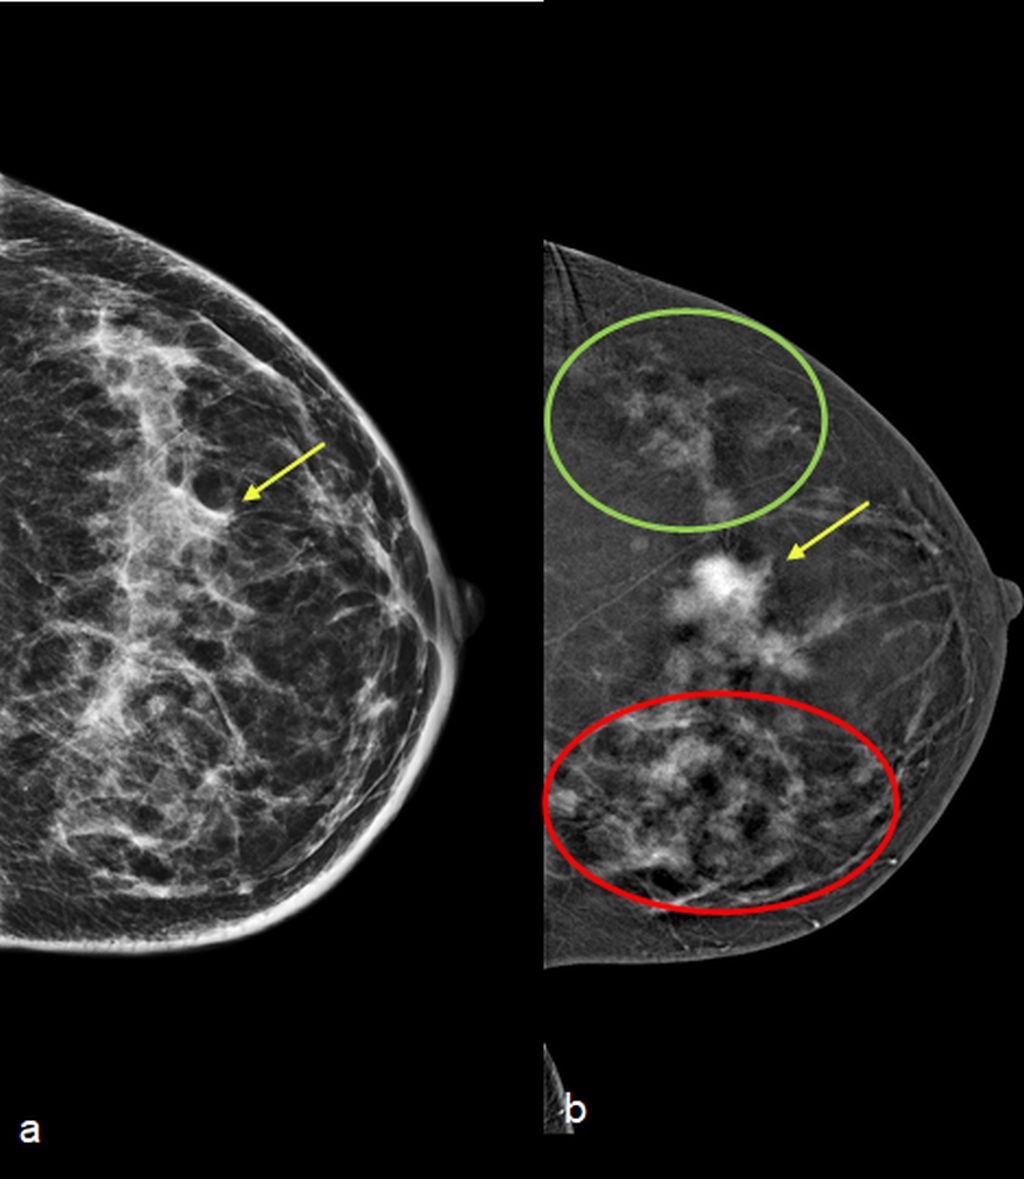

Low energy 2D mammogram images of both breasts in CC and MLO views (figure 1) demonstrate focal asymmetry with architectural distortion in the upper central quadrant of the middle third in the left breast with associated architectural distortion. Fine pleomorphic calcifications in regional distribution are noted in the inner central and upper inner quadrants of the left breast (figure 2). Diffuse skin and trabecular thickening is noted in the left breast. On post contrast recombined images (Figure 3), the area of focal asymmetry shows a heterogeneously enhancing mass with washout on delayed image (MLO). Heterogeneous and clumped non-mass enhancement in diffuse distribution is noted involving the areas of calcifications in the inner quadrant (red circle in figure 4) which could represent calcified ductal carcinoma in situ (DCIS) as well in the outer quadrant (green circle in figure 4) which could represent non-calcified DCIS. To differentiate between non-mass enhancement in diffuse distribution and background parenchymal enhancement, comparison with the opposite breast should be done. In our case there is minimal background parenchymal enhancement in the right breast (figure 3a and 3c) whereas clumped enhancement in diffuse distribution in the left breast (figure 3b and 3d) suggestive of non-mass enhancement in the left breast. Ultrasound correlation revealed an irregular isoechoic mass with indistinct margins with no posterior features measuring 2.2x1.9x1.6cm at 11:30 O'clock position, 6cm fn in left breast. It is hard on elastography (Figure 5). Non-mass ductal abnormalities in the form of irregular prominent and dilated ducts filled with soft tissue and echogenic foci within are noted in upper inner, lower inner and upper outer quadrants of left breast (Figure 6). The whole abnormality extends from the 8-12-3 o'clock position of the left breast. On tomo slices two equal density lesions with indistinct margins are noted in the upper outer quadrant of the right breast. On post contrast recombined images, they show heterogeneous enhancement. Ultrasound correlation revealed two hypoechoic lesions with circumscribed margins in the upper outer quadrant. Multiple enlarged left level I and level II lymph nodes are noted, which show asymmetrical cortical thickening and loss of fatty hilum (figure 7). MRI post contrast subtraction axial images (figure 8a and b) revealed a lesion with irregular shape and margins in the upper central quadrant of left breast with associated non-mass enhancement in diffuse distribution in upper inner, upper outer and lower inner quadrants confirming the mammographic extent of abnormalities (figure 8c).